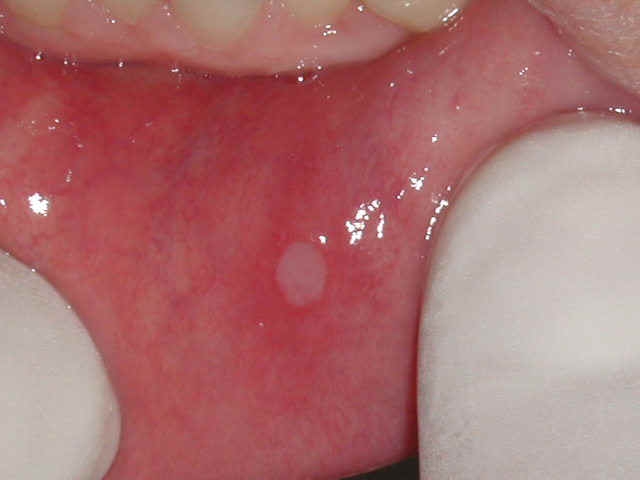

Cei care au suferit de afte bucale ştiu cât de supărătoare pot fi aceste mici băşicuţe pline cu lichid. Chiar şi după spargere, locul aftelor este luat de ulceraţii, care produc mâncărimi şi o durere sâcâitoare. Chiar dacă primul impuls pe care îl avem este să ne ducem la farmacie şi să luăm un produs împotriva ulceraţiei, este bine să ştim că avem o alternativă mult mai ieftină şi care nu lasă efecte secundare. Dacă aveţi la dispoziţie frunze de alun, de mur şi de salvie, problema este aproape rezolvată. Amestecaţi frunzele în proporţii egale. La un litru de apă, adăugaţi 3 - 4 linguriţe din amestecul rezultat şi fierbeţi-le. Clătiţi-vă de mai multe ori pe zi gura, timp de câte un sfert de oră, cu soluţia rezultată. Potrivit specialiştilor, efectele ar trebuie să apară încă din prima zi de utilizare.